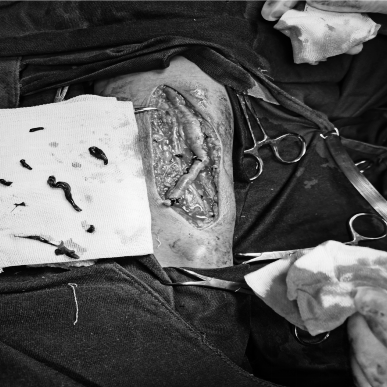

12月10日,贵州航天医院第87次晨读会由我院肾脏风湿科副主任医师谢谋进作学术交流,她以“系统性红斑狼疮”为题,全面讲解了该疾病的定义特征、临床表现与诊断标准、治疗原则及最新指南推荐等内容,并介绍了针对不同疾病活动指数的分层管理、非药物干预要点以及特殊阶段注意事项,为临床深化对该疾病的综合理解与规范实践提供了有益借鉴。 肾脏风湿科专家简介 冯远军 肾脏风湿、肝胆外科党支部书记,肾脏风湿科主任,主任医师 临床擅长:对慢性肾脏病、急性肾损伤、急慢性肾小球肾炎、肾病综合症、风湿性疾病、间质性肾炎、肾小管损伤等疾病的诊治及血液透析技术、动静脉内瘘成形术及疑难病例的诊治具有丰富的临床经验。 曾在上海市第一人民医院及贵阳市第一人民医院进修学习,贵州省医学会肾脏病学分会第五届委员会委员,遵义市医学会肾脏病学分会第一届委员会副主任委员,遵义市医学会风湿病学分会第一届委员会副主任委员,荣获“贵州航天劳动模范、遵义市汇川区先进工作者”,遵义市医疗事故鉴定专家库成员,主持省市级科研项目4项,完成4项,近5年发表论文10余篇,北大核心期刊1篇。 王卫华 肾脏风湿科主任医师 临床擅长:从事临床工作28年,擅长尿毒症患者血管通路的建设及维护(如标准和高位动静脉内瘘术、取栓+内瘘重建术、内瘘狭窄球囊扩张术、长期中心静脉置管术及肾穿刺活检术)等手术,对原发性和继发性肾病综合征、急、慢性肾小球肾炎、慢性肾脏病、泌尿系感染、结缔组织病、急性中毒、痛风、贫血、血小板减少症等疾病诊治及血液透析技术应用等具有丰富的临床经验。 1995年毕业于遵义医学院临床医学系,曾前往重庆医科大学进修学习肾脏疾病及血液净化,遵义市医学会肾脏病学分会常务委员,遵义市血液净化质量控制中心委员,先后发表肾病专业省部级医学刊物医学论文8篇,主持市级科研项目2项。 李丽华 中共党员,肾脏风湿科副主任医师 临床擅长:从事临床工作17年,对慢性肾脏病、急性肾损伤、急慢性肾小球肾炎、肾病综合征、风湿性疾病、间质性肾炎、肾小管损伤、急慢性肾衰竭的血液透析、CRRT治疗以及血管通路的建设维护等具有丰富的临床诊疗经验。 2006年毕业于遵义医学院临床专业,曾在遵义医学院附属医院完成住院医生规范化培养,并前往第三军医大学新桥医院、珠海市人民医院进修学习,中华医学会遵义市肾脏病学分会委员,遵义中医药学会肾病专业委员会委员,遵义市血液净化质量控制中心委员,遵义市医学会血液学分会委员会委员,发表省部级医学刊物医学论文4篇,主持参与省级科研课题1项,主持参与市级科研课题1项,院级新技术6项,获得本专业授权实用新型专利3项。 李 玫 中共党员,肾脏风湿科副主任医师 临床擅长:从事临床工作15年,对慢性肾脏病、急性肾损伤、急慢性肾小球肾炎、肾病综合征、风湿性疾病、间质性肾炎、肾小管损伤等疾病的诊治具有丰富的临床经验,擅长血液透析技术、动静脉内瘘成形术等。 2008年毕业于遵义医学院临床医学系,曾前往遵义医学院附属医院进修学习肾脏病与血液净化相关技术,遵义市医学会肾脏病学分会委员,发表肾病专业省部级医学刊物医学论文4篇。 谢谋进 中共党员,肾脏风湿科副主任医师 临床擅长:对肾脏风湿科常见病、多发病的诊治具有丰富的临床经验,特别擅长急、慢性肾小球、肾病综合征、系统性红斑狼疮、类风湿性关节炎、干燥综合征等疾病的诊疗,并熟练掌握CRRT、血液透析及血管通路的建立。 2010年毕业于遵义医学院临床医学系,2013年在遵义医学院附属医院完成住院医师规范化培训,曾前往四川大学华西医院进修学习;中国医师协会肾脏内科医师分会会员,遵义市医学会血液学分会委员会委员;发表省部级医学刊物、医学论文及科技核心论文数篇;主持参与院级新技术4项。 肾脏风湿科简介 基本情况 贵州航天医院肾脏风湿科2017年建立,住院患者承载能力达到50人左右,透析治疗服务惠及280余人的患者群体,在学科建设、高端医疗设备引进及专业技术队伍已达到区域内领先水平。科室共有医护人员46名,副高级以上专家7名,亚专业设置齐全,涵盖肾脏疾病、风湿免疫疾病药物治疗、透析治疗及透析通路维护等多个专业领域,为患者提供全面、精准、高效的诊疗服务。配备了尖端的医疗设备与智能化的辅助系统,包括透析机、CRRT机等设备。 专科特色 (一)肾脏病治疗领域:专精于血液透析、血液透析滤过、血液灌流、血浆置换、CRRT等尖端技术,致力于为患者量身打造个性化的肾脏替代治疗方案。 (二)在风湿病治疗方面:凭借生物制剂、免疫抑制剂等前沿药物,结合患者的具体情况,精心策划个体化的治疗策略,有效减轻患者症状,显著提升生活质量。 超声引导下球囊扩张术:内瘘狭窄是内瘘最常见的并发症之一,我们采用先进的超声引导下球囊扩张术,通过微创方式恢复内瘘通畅,有效避免了传统手术带来的创伤和痛苦。 内瘘血栓溶栓治疗、取栓术:血栓形成是内瘘功能丧失的主要原因之一,根据患者具体情况,采用溶栓治疗、取栓术等多种手段,确保患者及时恢复透析治疗。 内瘘动脉瘤形成治疗:动脉瘤是由于内瘘局部血流动力学改变引起的血管扩张性疾病,采取佩戴弹力绷带、手术修复等措施,防止动脉瘤进一步发展和破裂。 内瘘感染治疗:内瘘感染是内瘘并发症中最为严重的类型之一,一般采用敏感抗生素进行抗感染治疗,严重者采取手术清创等措施。 内瘘窃血综合征治疗:是由于内瘘建立后,远端肢体血流减少引起的一系列症状,通过调整透析方案、改善内瘘血流分布及必要时重建内瘘等措施,有效缓解患者的症状并提高其生活质量。 诊疗范围 擅长治疗急慢性肾炎、肾病综合征、肾衰竭等肾脏疾病;擅长治疗类风湿关节炎、系统性红斑狼疮、干燥综合征等风湿免疫性疾病,并为患者提供健康教育与康复指导,帮助患者更好地管理疾病,提高生活质量。 end